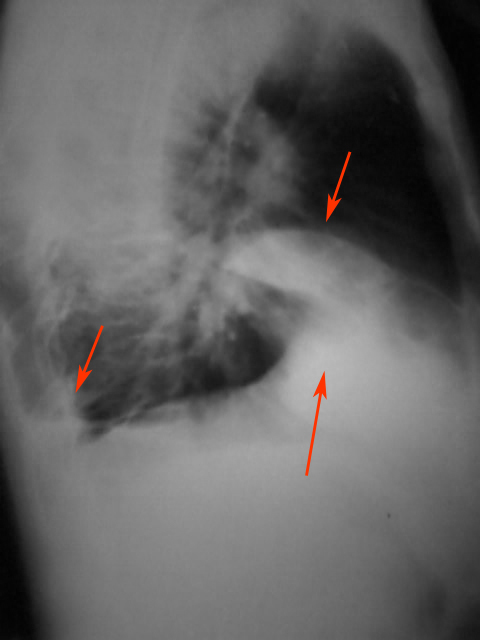

患者男,54岁,咳嗽咯痰伴右胸疼痛5天余.体温正常,一般情况尚可,否认咯血史

右中叶片状均匀高密度影,边界清楚,肺门区为见明显肿大的阴影,考虑右中叶综合征,更倾向于炎症,完善必要的实验室检查。

右中叶片状均匀高密度影,边界清楚,考虑右中叶综合征,做个ct吧

右肺中叶占位性病变伴右肺中叶不张。

右肺中叶外段炎症,右胸腔积液

右肺中叶炎症,性质待查.右胸腔积液

综合观察.叶间积液并包裹性积液.右下炎症,胸膜肥厚.

右侧胸腔积液伴右侧水平裂叶间积液;胸膜肥厚;左肋膈角改变,考虑胸膜粘连可能大.各位老师好!能结识此网站是我的荣幸!

右肺中叶炎症并膨胀不全,右侧胸膜炎。